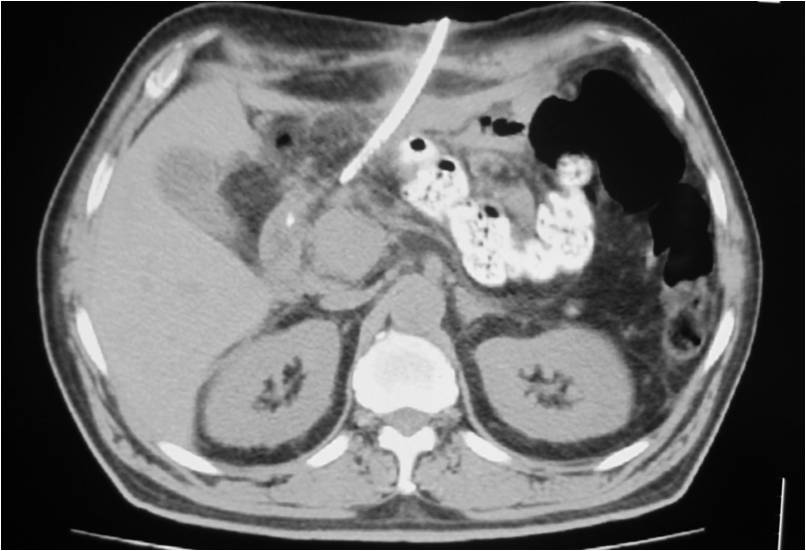

PATIENTS AND METHODS: During the last two and a half years, 93 post-operative patients were referred to the CT department for drainage of a post-surgical abscess in the abdomen or pelvis at 9-21 days post-operatively due to persistent fever. A total of 95 abscesses were drained; 84 were located in the abdomen and 11 in the pelvis. Abscess diameters ranged between 2 and 12 cm. A percutaneous drainage technique under CT-guidance was employed in all patients; 98 catheters were placed with use of the Seldinger technique. A transgluteal paracoccygeal approach was adopted in 11 patients. Aspiration of an intra-loop abscess was performed in 1 patient. The tilted gantry technique was utilized in 2 cases.

- Placement of two sump catheters in a abdominal abscess (surgery of inflammatory bowel disease), displacement of upper one